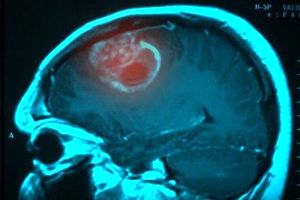

دانشمندان انگلیسی با همکاری محققان هندی مدعی شدند علت اصلی ابتلا به سرطان مغز را کشف کردهاند.